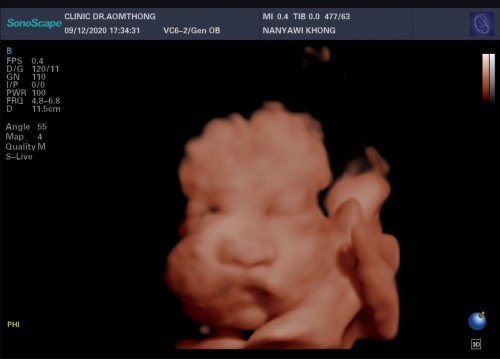

บ้านนี้กำหนดคลอด ก.พ. อยากเห็นลูกแล้วตื่นเต้น ไปซาวด์ 4D มา มีแก้มเยอะคุณหมอแอบแซว ชอบเอามือ เอาแขนบังหน้า 🤣🤣 แม่ๆคนไหนซาวด์แล้วเอาลูกมาอวดกันค่ะ